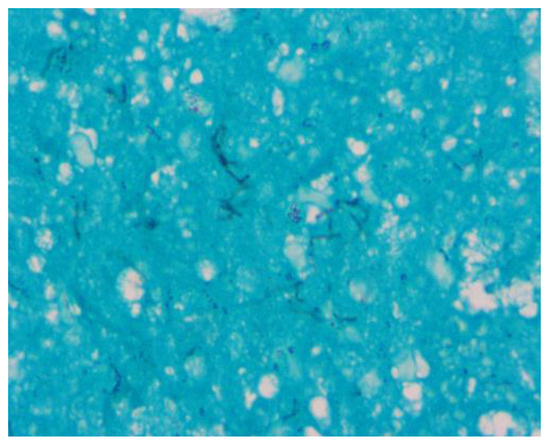

Introduction: Hypertension is occasionally associated with congenital hydronephrosis. Case report: The authors report a four-month-old boy with severe left congenital hydronephrosis and transient hypertension triggered by his first urinary tract infe...